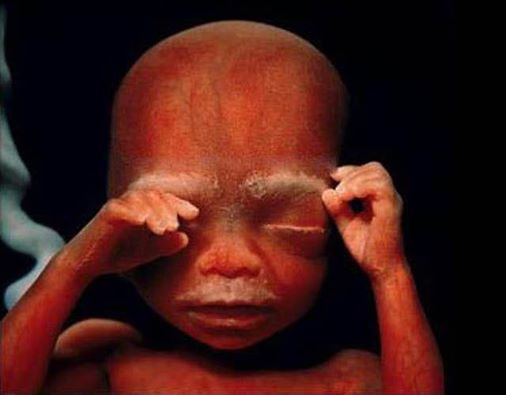

Dvadeset i četvrta nedelja

Šest meseci

19 Šest meseci: Mali čovek se sprema da napusti matericu